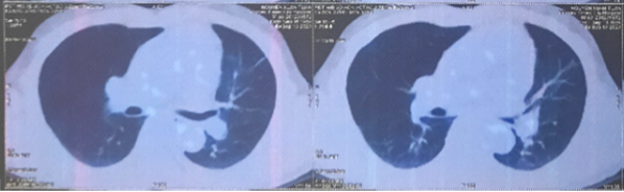

- Cắt lớp vi tính lồng ngực có tiêm thuốc cản quang:

Hình 1. Khối u kích thước 51x58x42mm thùy trên phổi trái, ngấm thuốc không đều sau tiêm (vòng tròn đỏ).

Hình 2: Vài nốt đặc nhu mô phổi 2 bên, kích thước lớn nhất 5x6mm